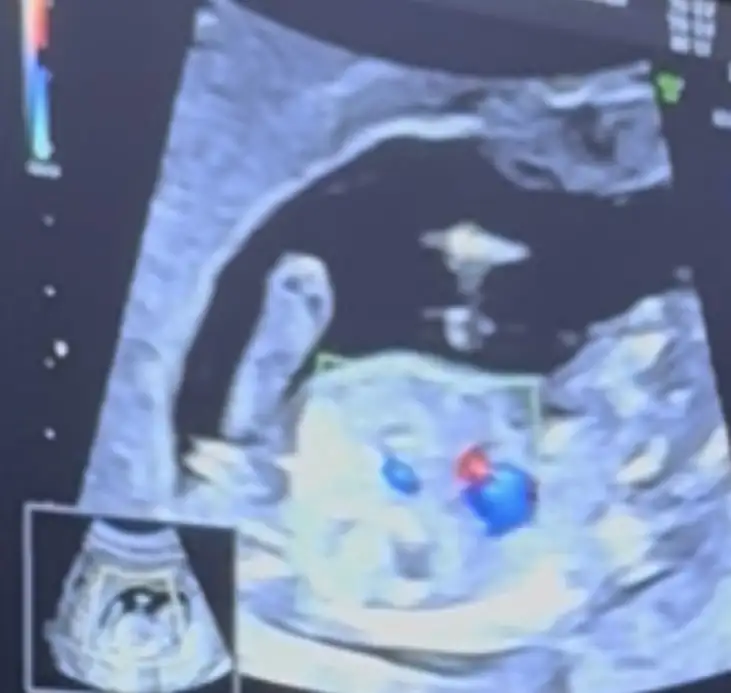

Kiza benzettim ama erkege de benzettim yamerhaba bugün tam 13hafta cinsiyet tahmininiz var mıEki Görüntüle 3619011 Eki Görüntüle 3619012 Eki Görüntüle 3619013